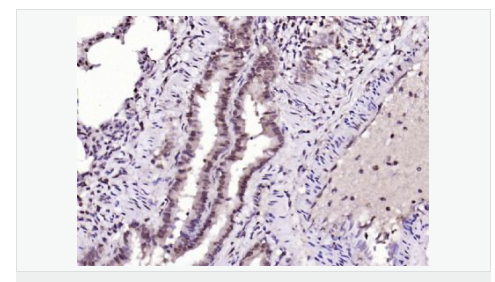

| 產品應用 | ELISA=1:5000-10000 IHC-P=1:100-500 IHC-F=1:100-500 IF=1:100-500 (石蠟切片需做抗原修復) not yet tested in other applications. optimal dilutions/concentrations should be determined by the end user. |